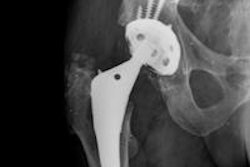

An example of 3D modeling performed with the EOS system for the assessment of total hip arthroplasty. Image courtesy of Dr. Cyrille Delin.Relatively few published studies have sought to optimize the dose received by patients during exploration of the lower limbs, particularly the hips, so thestudy team sought to calculate and compare the doses of ionizing radiation delivered to the organs by CT and SR during measurements of lower limb torsion and anteversion.